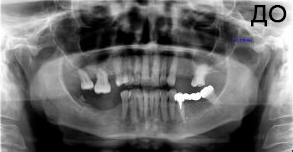

4 работы в портфолио

Акопян Антон Владимирович: портфолио (4)